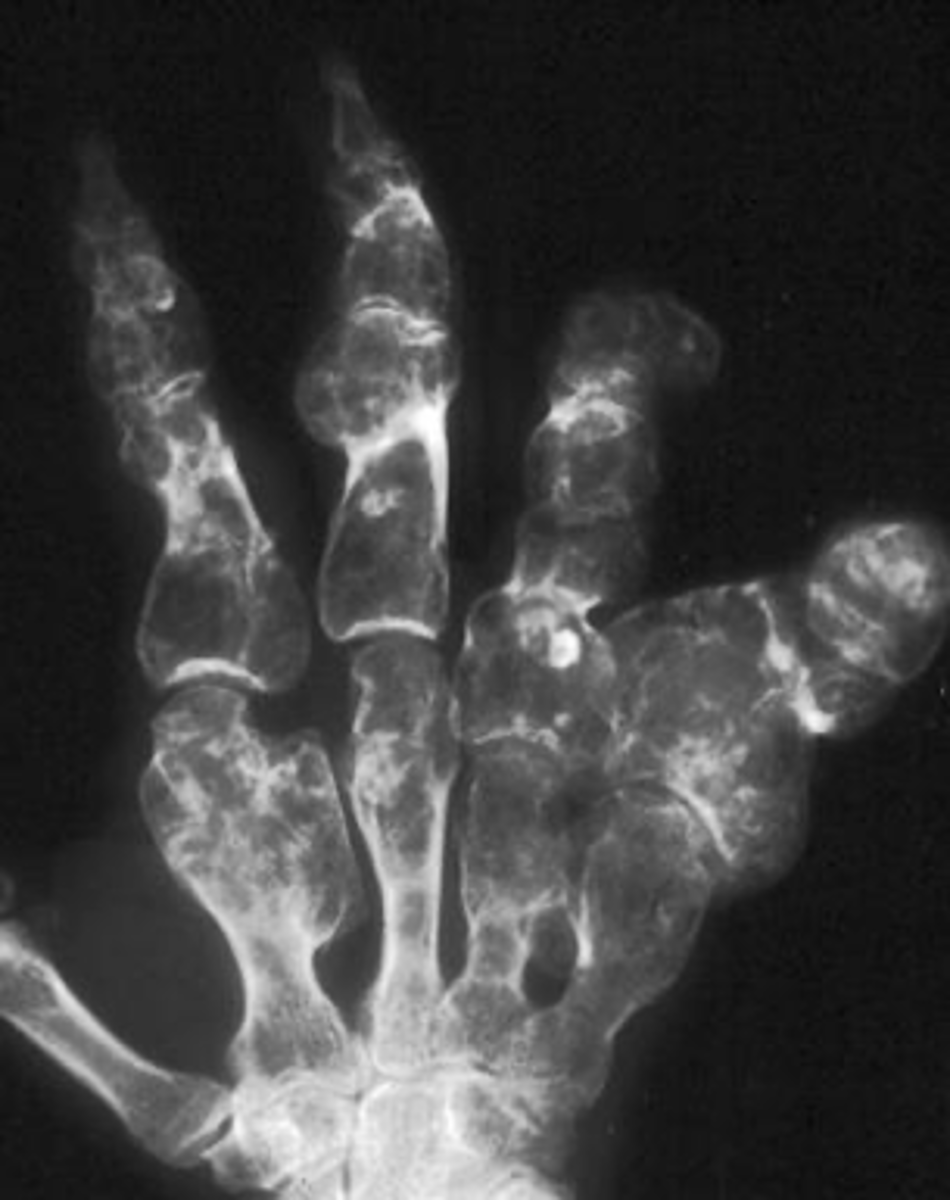

Multiple enchondromas

ID benign tumor